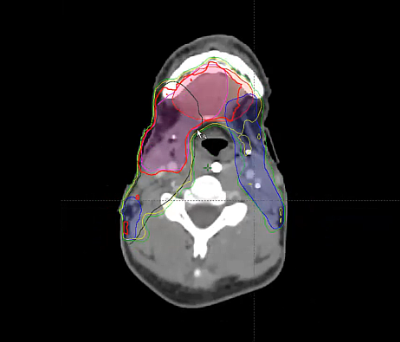

retropharyngeal lymph node, supraclavicular nodes, PET, dosimetry, GTV, QUAD SHOT, CPS, non metastatic, immunotherapy, sinonasal carcinoma